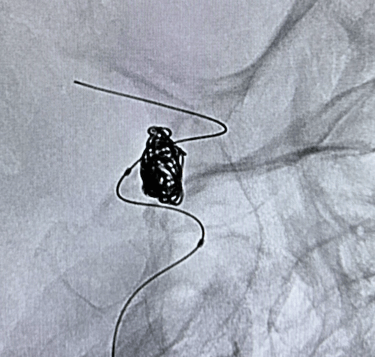

Neurocirurgia endovascular

Aneurisma cerebral;

Malformações arteriovenosas (MAVs);

Tratamento de doenças vasculares do cérebro e da medula espinhal por meio de técnicas minimamente invasivas — realizadas por cateteres, sem a necessidade de incisões cirúrgicas.